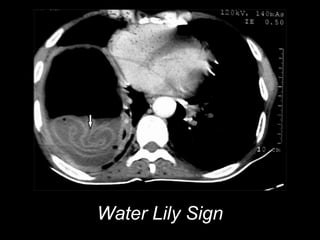

Water Lily Sign

• #45 Water Lily Sign

• #46 Water Lily Sign